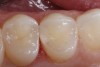

Figure 3. An occlusal view of tooth numbers 18 and 19 after anatomic placement of the enamel “capping” layer (Xtra-Fil: VOCO America), finishing, and polishing.

Figure 3